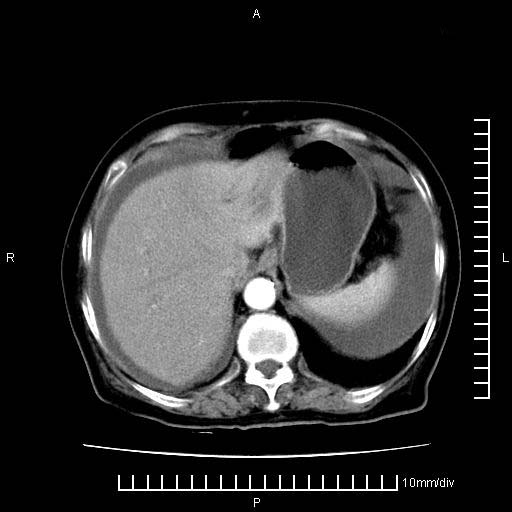

上腹疼痛月余,外院核磁诊断胰腺癌。现临床示右下腹可明显触及包块,可片子上怎么没有看到?

1。胰腺ca伴腹膜腔转移

2。肝左叶低密度灶,考虑转移可能

支持胰腺癌肝内转移,腹水改变。

胰腺结构模糊,胰尾部见囊性包块,周围脂肪密度增高,左肾前筋膜增厚,胸水、腹水。不符合胰腺ca伴腹膜腔转移。考虑胰腺炎伴假性囊肿形成、胸腹腔积液。

1、考虑胰腺癌伴腹膜腔转移,胸腹水。

2、肝脏转移可能。

1)考虑胰腺癌并胰腺假性囊肿形成。2)肝内低密度灶,不排除转移。3)右肾盂积水。4)腹水。5)右侧胸腔积液并右肺下叶部分膨胀不全。

考虑胰腺ca伴腹膜腔转移、肝左叶转移、右肾积水。右胸腔积液。